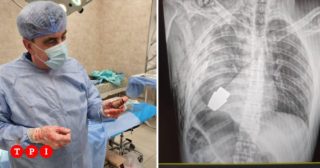

Come riporta il Guardian, nel corpo del soldato si trovava una granata russa rimasta inesplosa. L’operazione è andata a buon fine e il soldato di 28 anni è salvo. Si è trattato di un intervento molto difficile, dal momento che la granata avrebbe potuto esplodere, uccidendo, non solo il soldato, ma anche i medici presenti in sala operatoria.

Proprio per questo altissimo rischio, l’operazione è stata eseguita da uno dei chirurghi più esperti delle Forze Armate dell’Ucraina, Andrii Verba, senza elettrocoagulazione, che avrebbe potuto provocare l’esplosione della granata. Ora il soldato è in condizioni stabili, ma dovrà affrontare un lungo periodo di convalescenza.

Come riporta Repubblica, la viceministra delle Difesa ucraina Hanna Maliar ha pubblicato su Facebook un’immagine del corpo del soldato vista ai raggi X, in cui è perfettamente riconoscibile la granata: “Medici militari hanno eseguito l’operazione per rimuovere una granata di tipo Vog, che non si è rotta nel corso dell’intervento, dal corpo di un soldato”, ha scritto la viceministra.